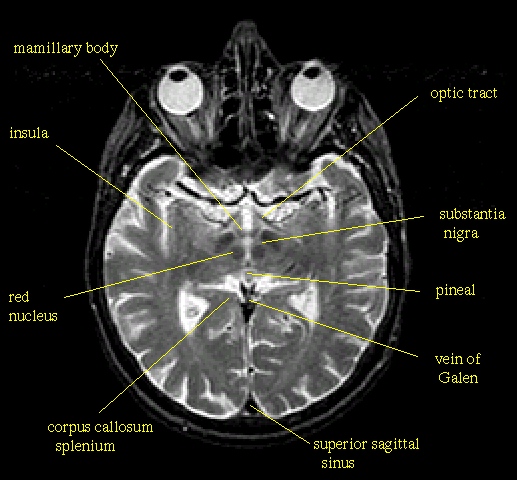

Schneidet man das Gehirn etwa in Höhe der Ohren bzw. dicht unter den Augen horizontal auf, dann ergeben sich das folgende Schnittbild (eine Computertomogramm- bzw. CT-Aufnahme), das nochmals die beiden Kortex-Teile, aber auch jenes schon angesprochene 'Breitbandkabel' - den corpus callosum - zeigt:

Schneidet man das Gehirn im Bereich der Ohren senkrecht auf, dann ergeben sich die folgenden Schnittbilder; auch hier erkennt man beide Male sehr schön oben unter dem Scheitel einen tiefen Einschnitt, der die beiden Hemisphären voneinander trennt; weiter unten im Schädel ist dann wieder jenes 'Breitbandkabel', der corpus callosum, zu erkennten: